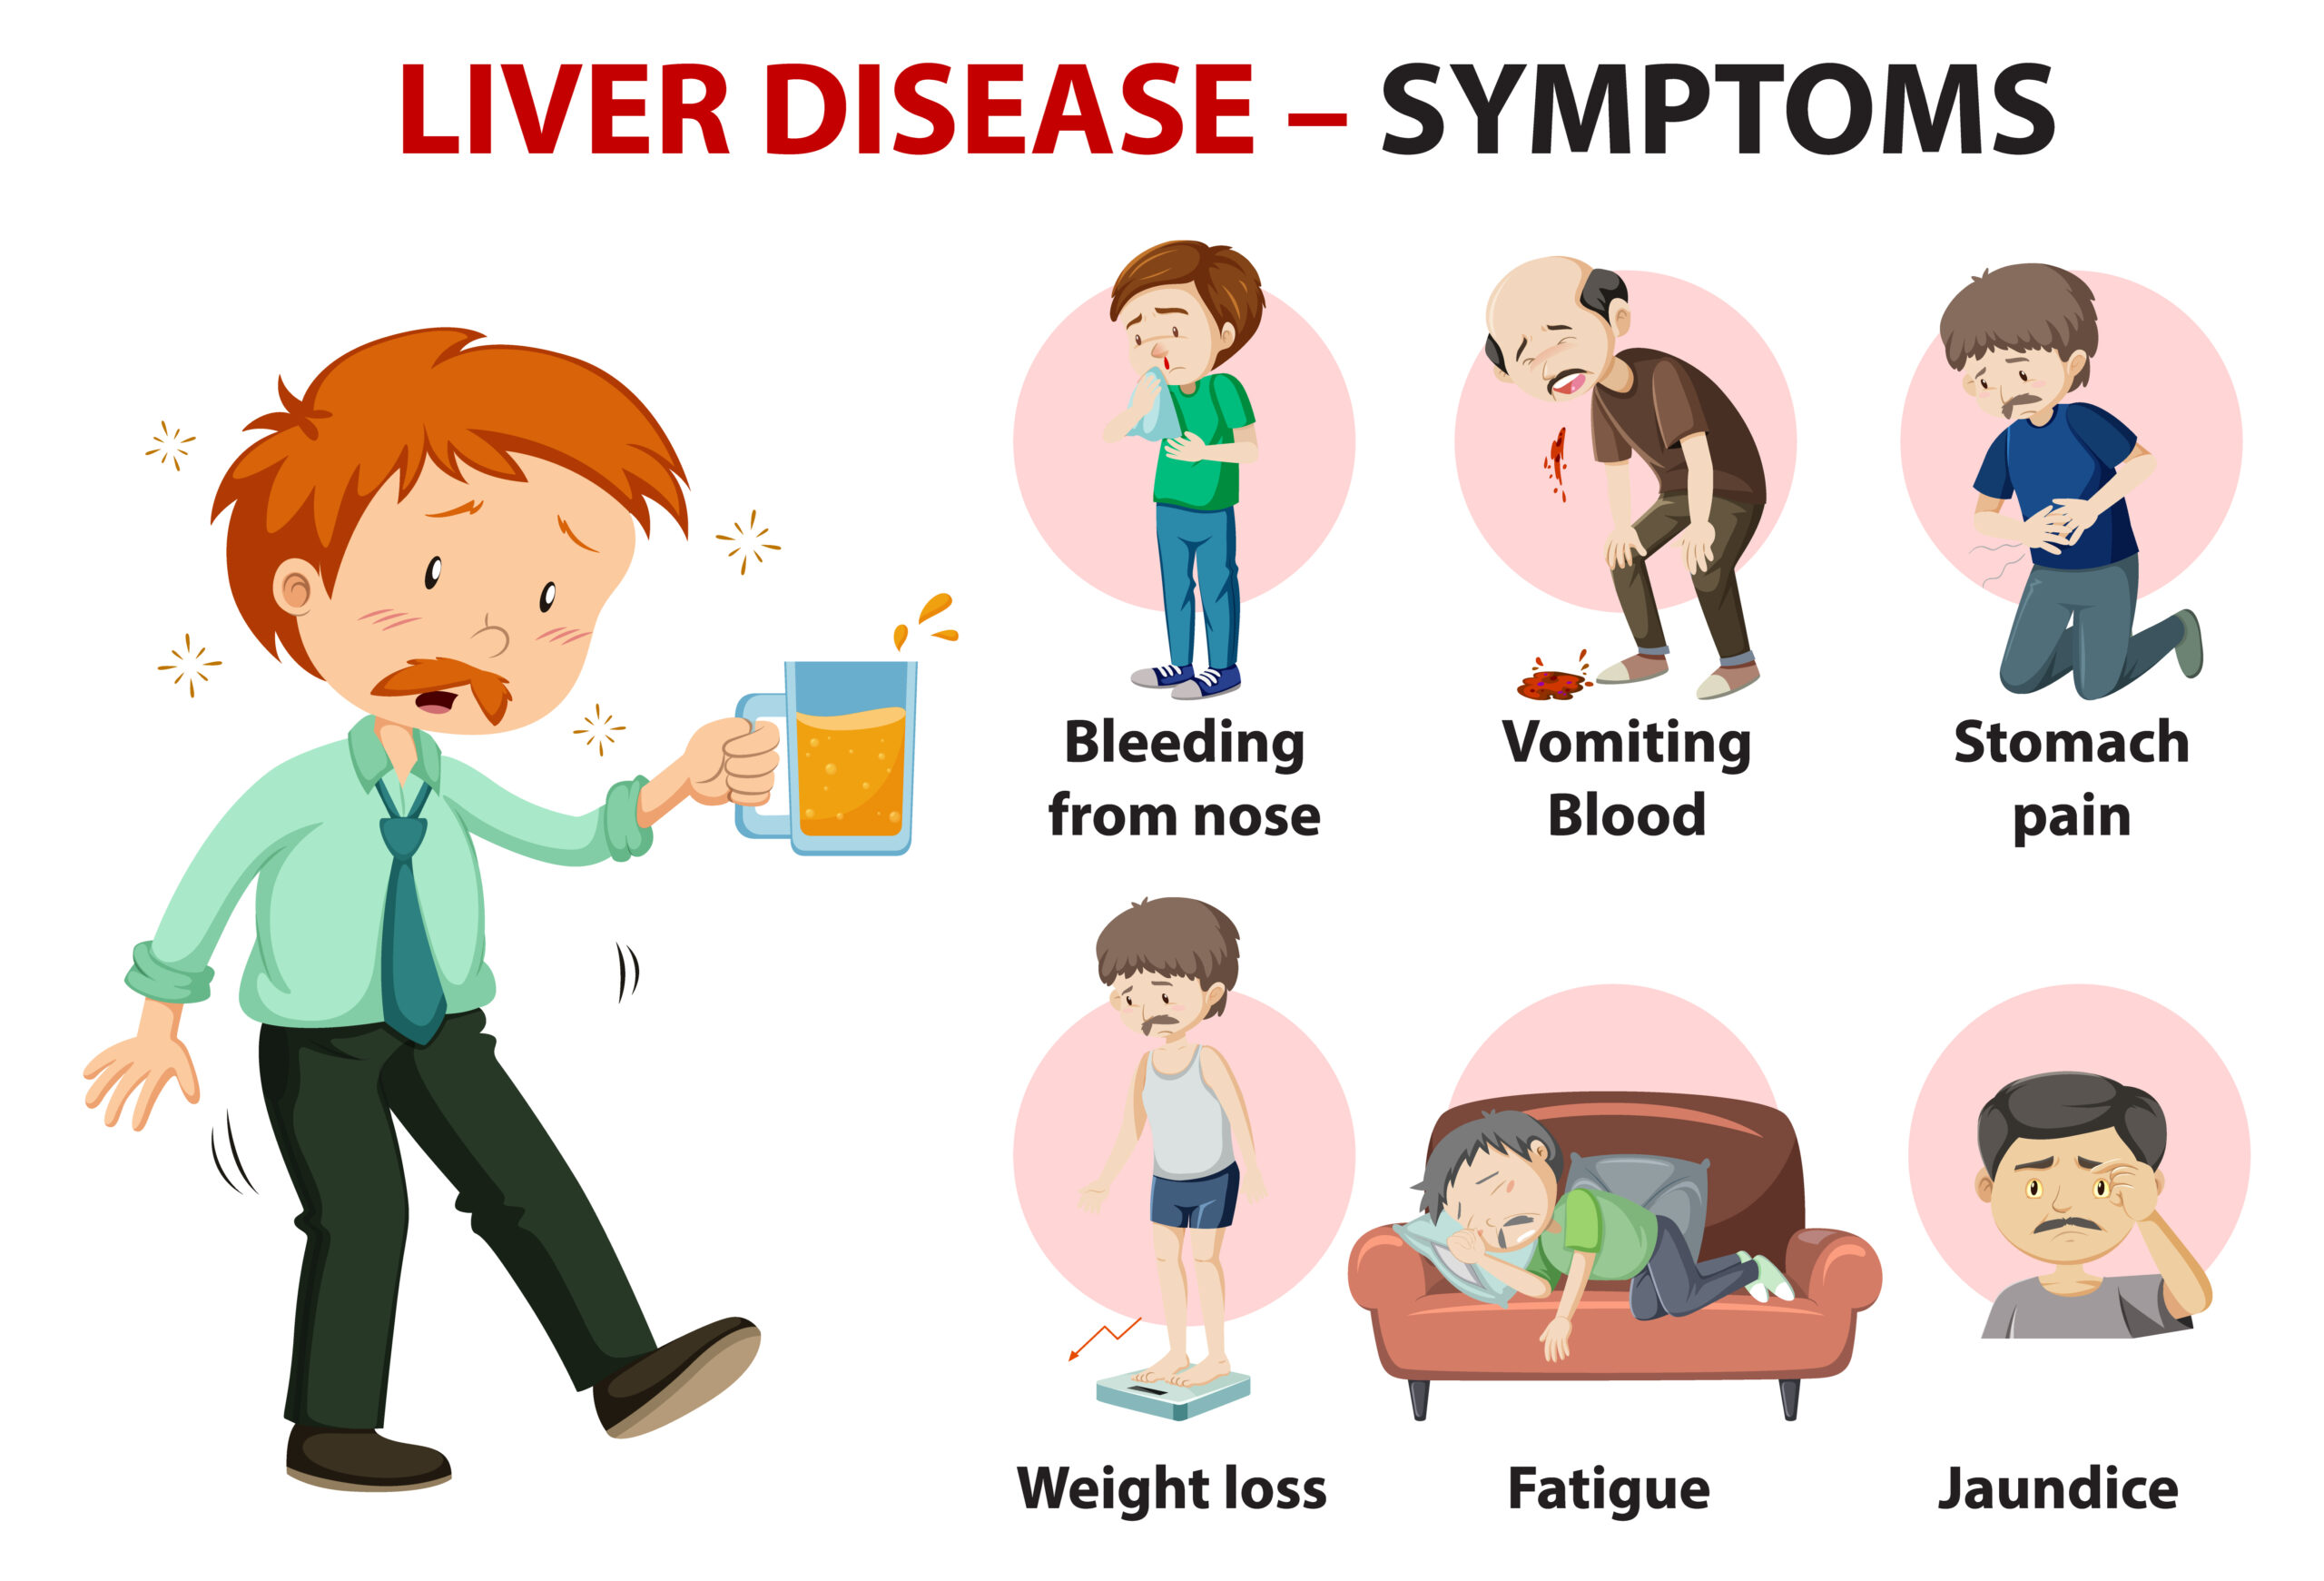

Symptoms Of A Bad Liver Function

Symptoms Of A Bad Liver Signs

Symptoms Of A Bad Liver In Humans